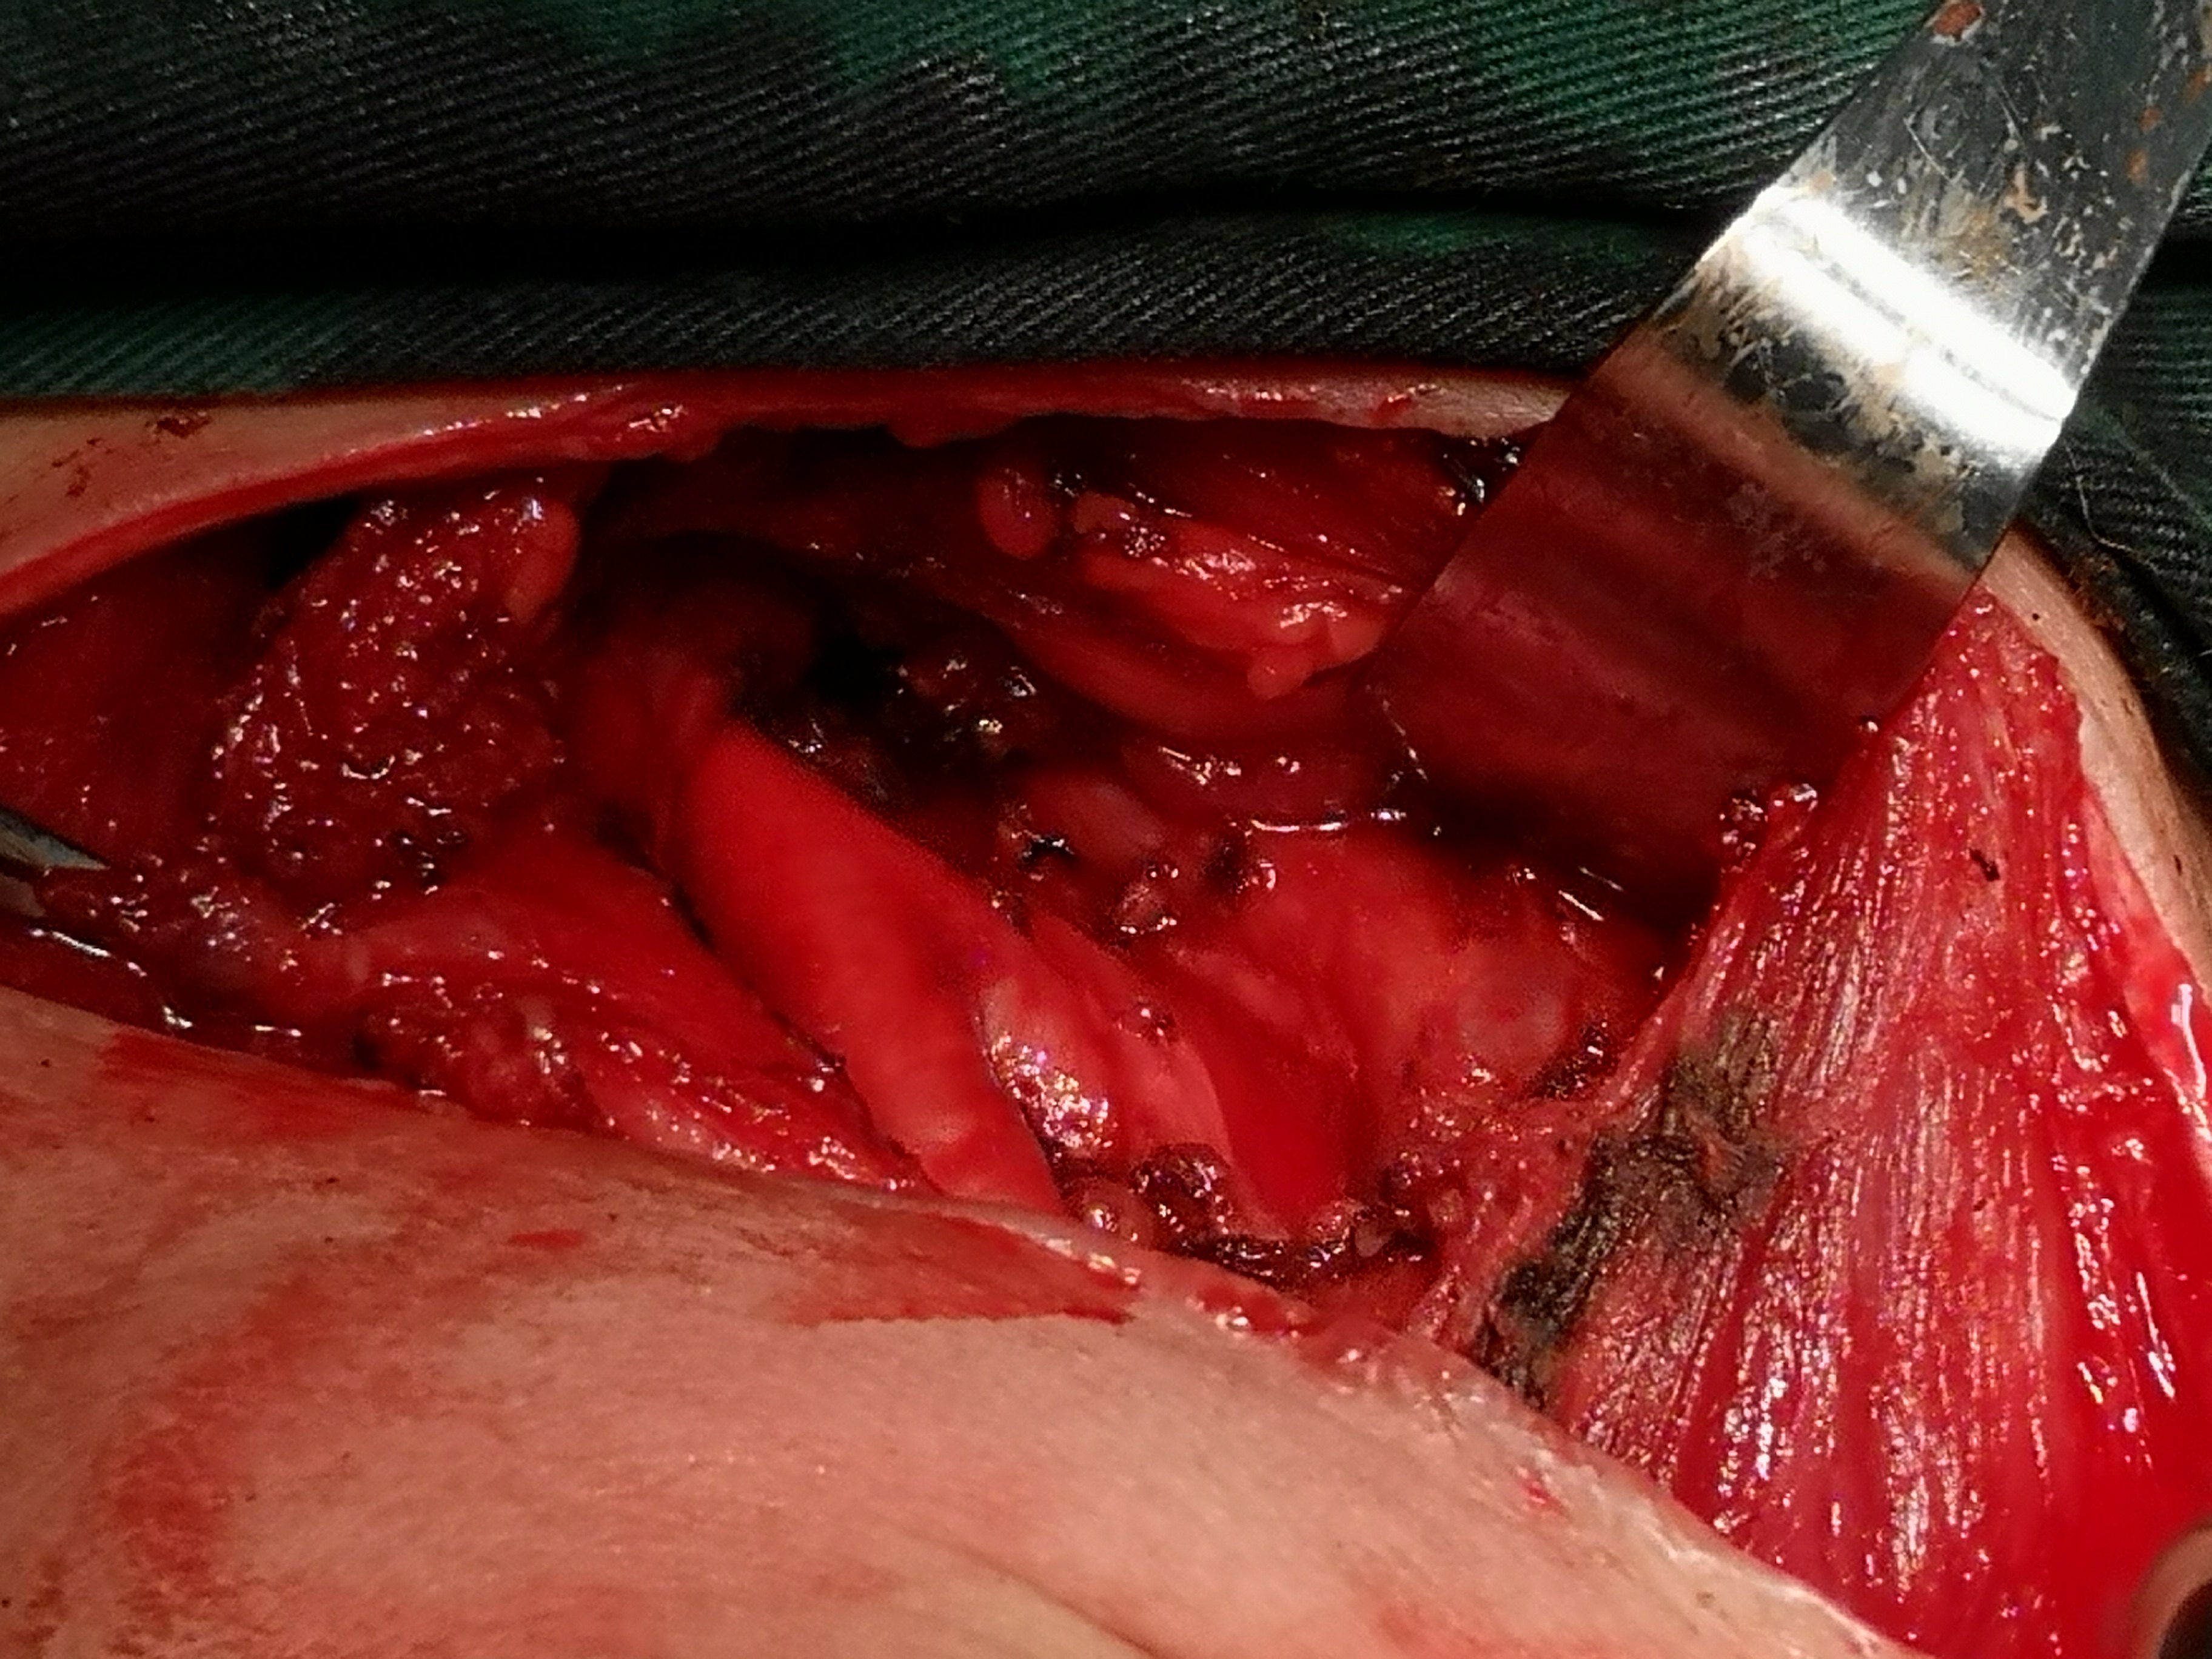

甲状腺癌再次手术

病例2 右2,右4R区,左6区残留,颈部切口清扫,未开胸